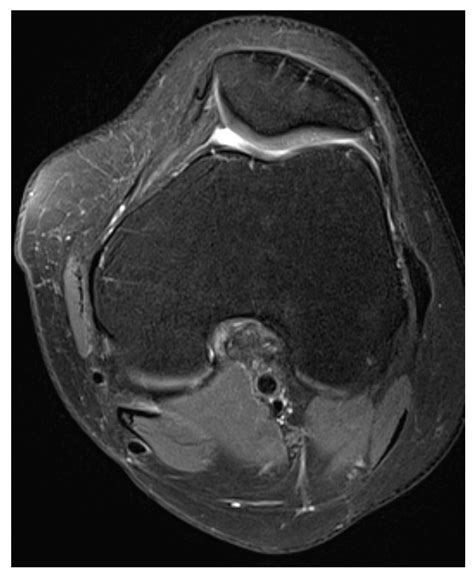

• Imaging Studies: X-rays, MRI, and CT scans can provide detailed images of the knee joint, helping to identify any structural abnormalities, fractures, or soft tissue injuries. MRI is particularly useful for visualizing the MPFL and other ligaments.